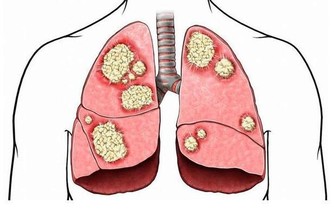

國慶假期前,陳先生去做了一次身體檢查,結果出來后他傻了眼:肝內總脂肪量佔到肝重的10%,輕度脂肪肝。

脂肪酸釋放難以分解,營養不良同樣會得脂肪肝

連雲港市第一人民醫院健康管理專家劉曉光在詢問了陳先生情況后,做出了解釋。其實脂肪肝分為酒精性脂肪肝和非酒精性脂肪肝,酒精性脂肪肝是長期飲酒造成的,營養過剩和營養不良都可能導致非酒精性脂肪肝。

據統計,約有22%的素食者會得脂肪肝,而這些人也大多是正常體型。劉曉光醫師稱,人體中所需要的能量主要來自三大營養物質,脂肪、蛋白質和碳水化合物。像陳先生這種純素食者,不吃魚肉蛋等營養物質,也就是少了動物蛋白質和脂肪來源,人體的白蛋白合成減少,就需要分解脂肪組織來維持營養均衡,大量的脂肪酸從脂肪組織中釋放進入肝臟后,而這種脂肪在肝臟中不易被分解,若不能及時排出,肝臟中的脂肪堆積過多,長期以往,就形成了脂肪肝。

不只是素食主義者有患病隱患,曾經有社區在湖北武漢對歸元寺、鐵佛寺的兩寺僧人進行體檢,結果令人大吃一驚:受檢的30名僧人中,接近一半的僧人的肝內總脂肪量佔到肝重的5%-10%,達到輕度脂肪肝的標準。

脂肪肝已成為人類第一大肝病

目前,世界各地的脂肪肝的發病率逐年上升,發病年齡也越來越小。它可能發生於各個年齡段,以40-50歲最為常見。酒精性脂肪肝男性患者居多,非酒精性脂肪肝過去認為以女性為主,近年來認為男女發病率幾乎相當。在發達城市,成人脂肪肝的患病率更是超過了30%,主要病因就是營養過剩和酗酒,所以脂肪肝又被稱為「富貴病」。而在一些貧窮地區,由於蛋白質、熱量攝入不足也會引起脂肪肝。通過上文所知,脂肪肝不只是胖子的專利,瘦人也可發生。